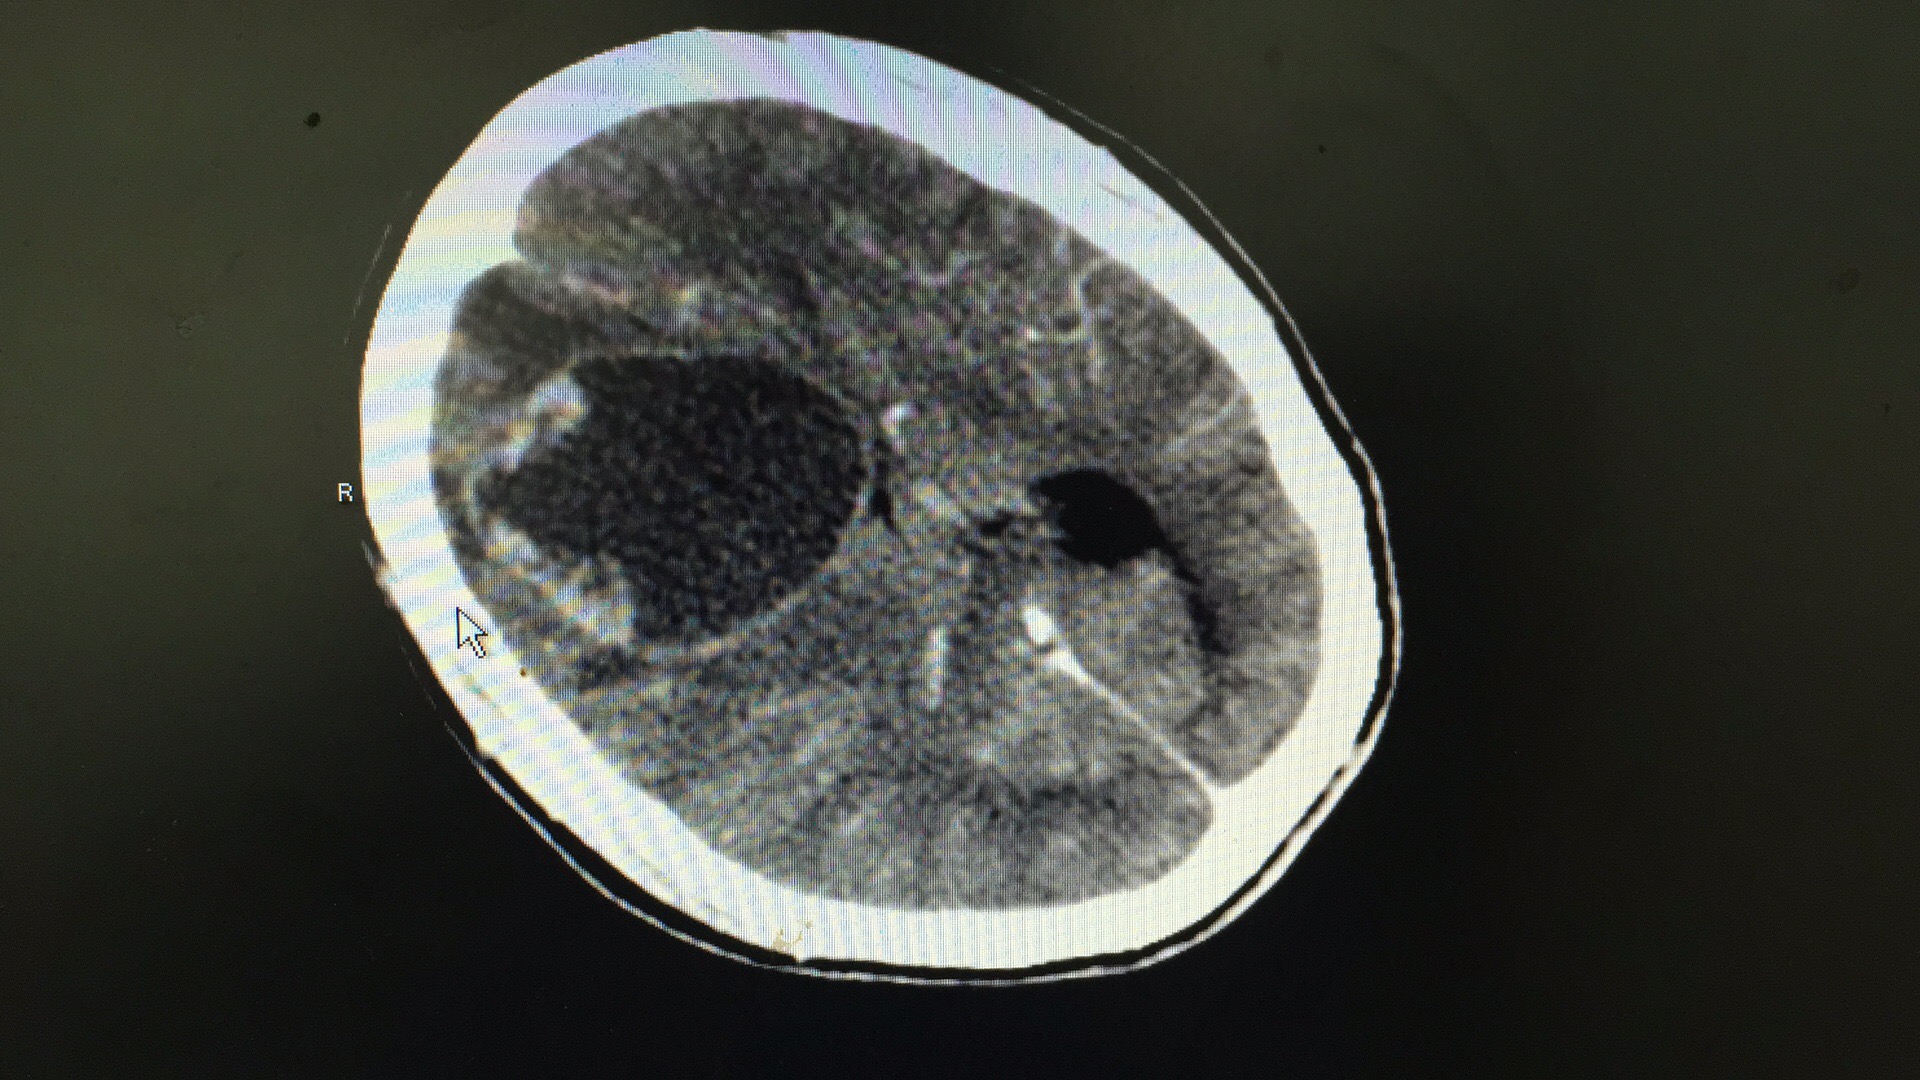

病人术前片